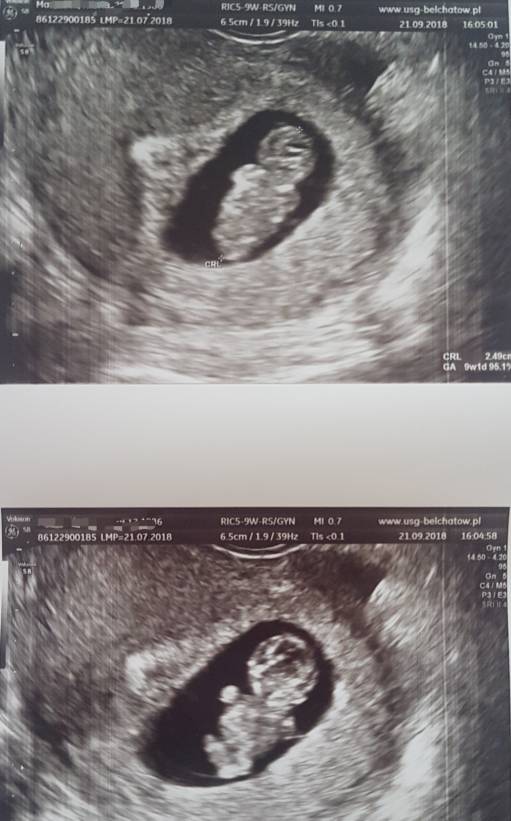

Ostatecznie zmieniłam lekarza i jestem mega zadowolona. Poprzedni podchodził do pacjentek powiedzmy że finansowo. Dzisiejsza wizyta zmieniła mój światopogląd o lekarzach. Za wizytę zapłaciłam tyle samo Ale trwała ona 45 minut. Lekarz dokładnie przeprowadził że mną wywiad, zapytał jak się czuje czy mam jakieś dolegliwości, jaka mam pracę. Przejrzał raz jeszcze wszystkie badania i kazał powtórzyć Toxoplazmoze. Przeprowadził dokładne badanie usg podczas którego wszystko objaśnia i wytłumaczył.

Czułam się komfortowo dopieszczona ( jako pacjentka) i uspokojona.

Bobas to chyba cały tata... wierci się niesamowicie [emoji16] ma 2, 49 cm -czyli jesteśmy w 9t1d. Tętno 169.

Badania prenatalne 16.10.

Poniżej zdjęcia maluszka